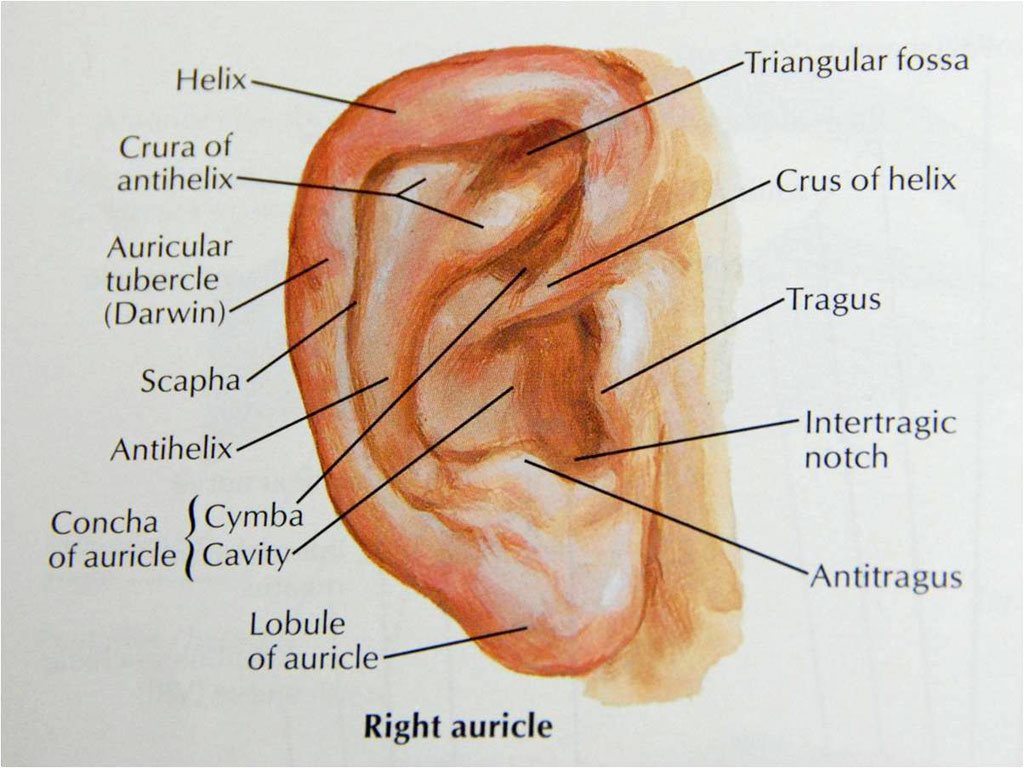

A conchal setback is when the Concha is sewn back to the tissues behind the ear to make the ear more pinned back during an otoplasty or cosmetic ear reshaping procedure (Dr Young is a Facial Plastic Surgeon in Bellevue Washington). Many times a prominent ear is due to the conchal bowl being to developed and strong. The tissues behind the ear are reduced and then the ear is sewn backward to make the ear appear smaller. Take a look at the picture below to see what I mean by the concha. I have found over the years watching many famous surgeons who do ear reconstruction, otoplasty like Dr Reinish and Dennis Crockett in Los Angeles when I was training in LA and Dr Burt Brent in Woodside California that there are a lot of different techniques out there. I have found that just removing the tissue behind the ear is not sufficient a lot of times to make the ears more pinned back. I have found that shaving the concha cartilage down incrementally is essential to allowing the ear to more easily and more permanently be pinned back towards the head. What I learned is that you need to be very incremental in how much you shave. There should be a little tension in the cartilage when you pin in back otherwise the results can be less predictable. As show in the picture below, I use a scalpel to take down the cartilage a little at a time and I usually reassess after every short session of debulking the conchal cartilage. The scalpel is shown pointing to the areas where I have taken down the cartilage. The first picture is the general anatomy of the ear. The second picture shows the back of the ear displaying mostly the concha cartilage. The third picture shows the concha after it has been shaved down. The fourth picture illustrates the cauda helicis or the tail of the helix cartilage that is responsible for protruding the ear lobe. The forceps or pincer instrument is grabbing the cauda helicis that is reponsible for earlobe protruding. This cartilage can be excised or taken away or it can be sutured to the concha more to cause the earlobe to be more pinned back as well. These pictures also illustrate that most otoplasty techiniques are carried out from an incision that is from the back of the ear. This keeps the incision well hidden so that evidence of surgery is hidden and you can avoid looking like you had something done. The last two pictures are some before and afters for you to see what the results are after you get an otoplasty / ear cosmetic shaping procedure.